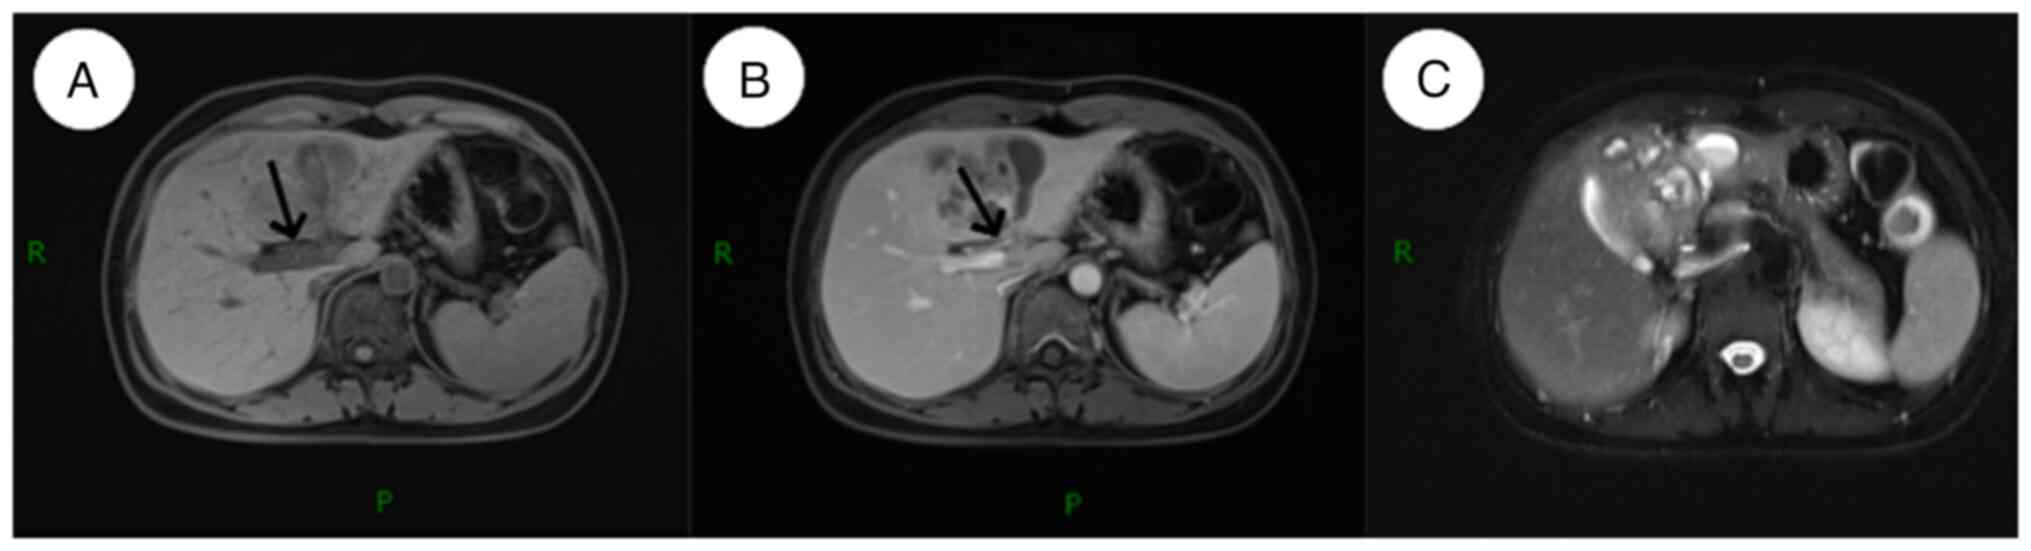

On hepatobiliary and pancreatic magnetic resonance imaging (MRI), 78x7-mm mixed long T1 and T2 signals were observed in the left lobe of the liver on a plain scan. The signal was uneven with a poorly defined edge, and a small patch of short T1 signal was visible. T1-weighted imaging (T1WI) indicated a low signal, while T2WI indicated a high signal. Enhanced scanning revealed progressive mild to moderate uneven enhancement in the lesion area. The central necrotic area was not enhanced, and a small patch of edema was observed around it (Fig. 2). The diagnosis was of a suspected liver abscess, and a neoplastic lesion needed to be excluded based on a combination of the clinical symptoms and examination findings. The postoperative pathology did not reveal tumor cells.

Figure 2

Preoperative abdominal magnetic resonance imaging examination results. (A) T1WI results showing the tunnel sign (arrow). (B) Gadolinium-enhanced T1WI results showing tunnel wall enhancement, with no enhancement in the tunnel itself (arrow). (C) T2WI results exhibiting high signal intensity and diffuse mildly dilated terminal bile ducts can be seen both in the center and periphery of the lesion. WI, weighted imaging; P, CT section was started from the posterior side; R, CT section was started from the right side.

In previous years, with the progress of medical imaging technology, CT and MRI have been widely used in the diagnosis of parasitic infections of the liver and biliary tract. Due to the non-specific clinical symptoms of Clonorchis sinensis infection, solely relying on the clinical presentation for diagnosis is challenging, emphasizing the importance of characteristic radiological findings (14). MRI findings typical of Clonorchis sinensis infection include diffuse dilation of the intrahepatic peripheral bile ducts, with larger and extrahepatic bile ducts remaining undilated (14,15). In the present case, high signal was observed on T2WI, and diffuse mildly dilated terminal bile ducts were observed both in the center and periphery of the lesion. This characteristic is attributed to Clonorchis sinensis predominantly infesting the terminal bile ducts, causing obstructions in the smaller peripheral ducts (13). The most common finding on MRI of Clonorchis sinensis is a diffuse mild dilatation of the small intrahepatic bile ducts without dilatation of the extrahepatic bile ducts (15). The patient in the present report exhibited small patchy low-density lesions within the liver on the preoperative abdominal CT, with enhanced margins and septation upon contrast scanning. The hepatobiliary and pancreatic MRI findings included mixed long T1 and T2 signals, inconsistent signal intensities with indistinct borders, small patches of short T1 signals, low signal intensity on T1WI and high signal intensity on T2WI. The enhanced scans revealed a progressive, mild to moderate, uneven enhancement within the lesion area.